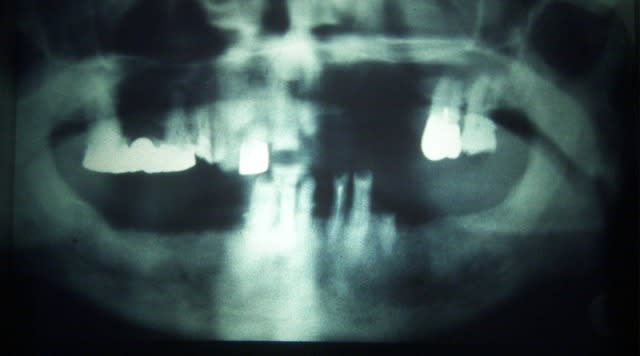

Merci Olivier, dans la série c'est dans les vieux plats que l'on fait la bonne soupe, même si les "jeunes" préfèrent les packs, un autres cas qui montre que les implants ne sont pas tous de simples trucs tout ronds à visser:

Et surtout que la gestion paro prothèse était déjà importante fin 80.

Ce cas à m'a permit de former ma prothésiste, débutante de moins d'un an, à un travail sur implant. (ceramik doucement, le cadcam n'existait pas)

les implants etaient:

haut:D2 Tatum (3.5x5x20mm)

P4 Tatum impacté (4x17)

TBR (lisse...) 13mm je crois

Bas: 2 Lames TBR grand modèle

2 D3 Tatum (3.5x7x20mm dont 1 racourci à la pose)

2 R4 Tatum (4x20mm)

posés en une scéance, au fauteuil!

un peu bourin à l'époque